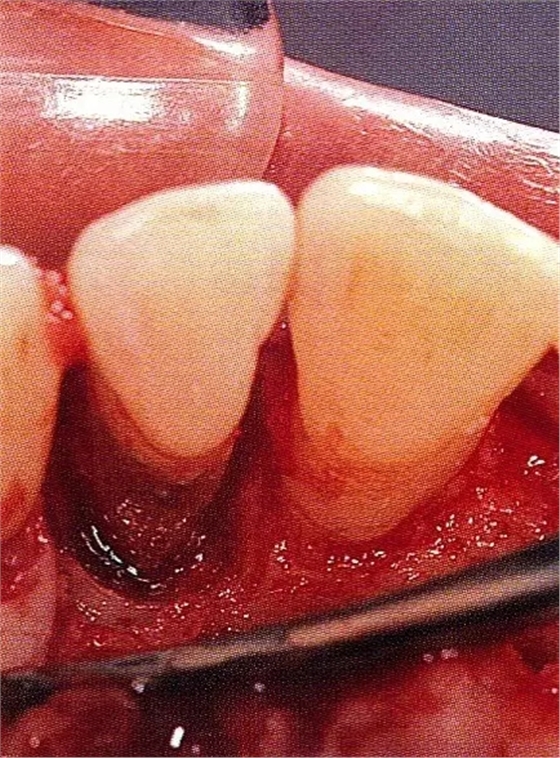

▲圖7-3將posterior interproximal類型的非吸收性覆膜修整后進(jìn)行垂直懸吊縫合做固定。垂直懸吊縫合后,確定覆膜是否會(huì)動(dòng)搖,再將齦瓣與之緊密縫合。